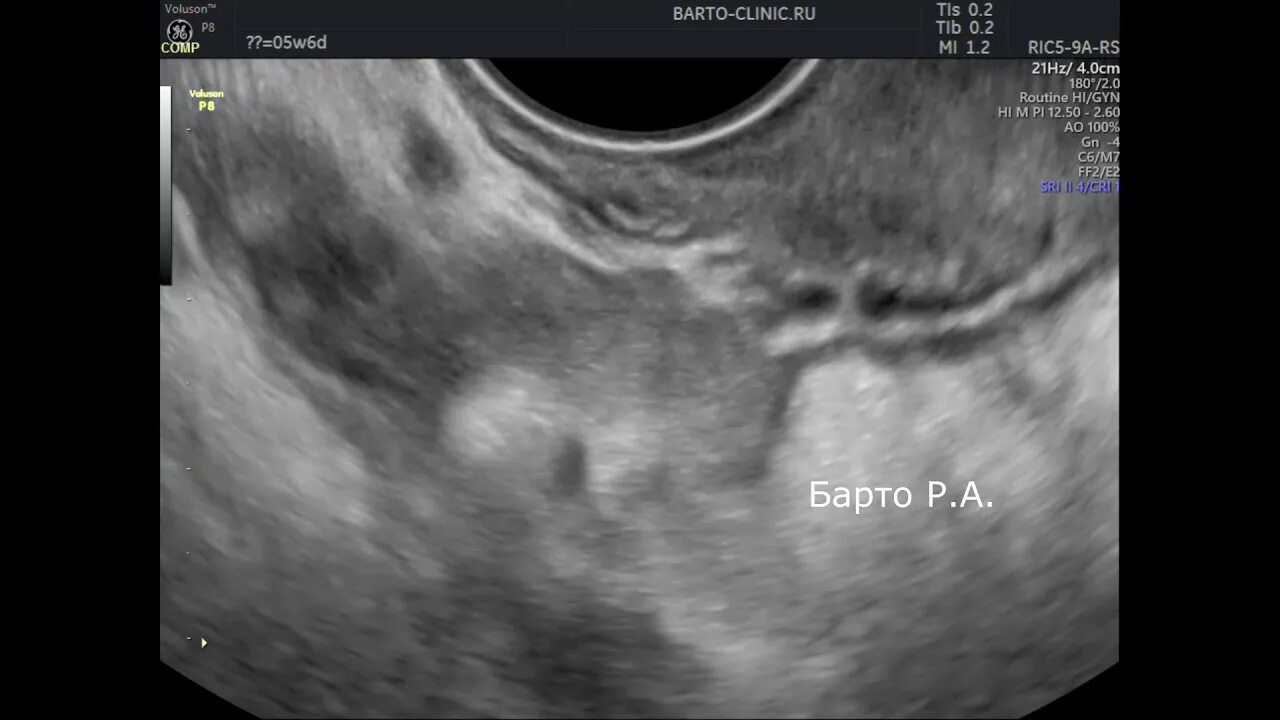

Аномальная беременность